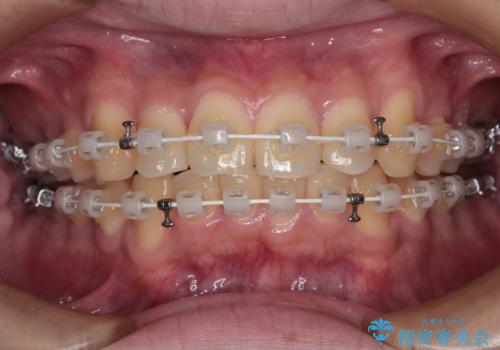

- 矯正装置

- 審美装置

- 上下前歯の捻れやデコボコを気にして来院された患者様です。

マウスピース矯正でもワイヤー矯正でも対応可能でしたが、極力楽をして治したいとのことでワイヤー装置にて治療をおこなうこととしました。

口元はそれほど突出しておらず、患者様自身も気にしていらっしゃいませんでしたが、前歯の捻れやデコボコを解消すると、前方に拡大され、治療後に出っ歯仕上がりとなるリスクがあったため、補助装置により上顎臼歯を後方移動していくこととしました。

昼休みを活用して通院してくださり、1年半であっという間に終えることができました。